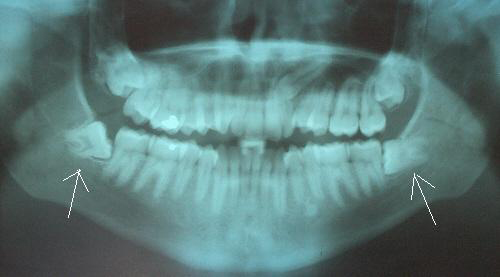

Oral Diagnoz ve Radyoloji